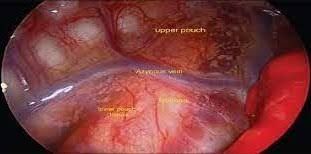

قیمت: 25٬000 تومان - دسته بندی فایل: تحقیقپاورپوینت عروق قفسه سینه آئورت (ppt) 12 اسلاید

فروش ویژه پاورپوینت حرفه ای عروق قفسه سینه آئورت / تعداد اسلاید: 12 اسلاید